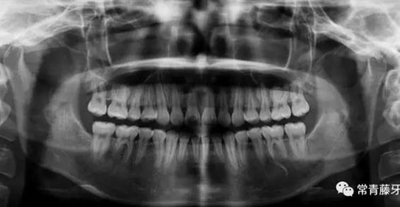

影像學(xué)檢查

曲斷顯示38、48阻生;雙側(cè)TMJ髁突頭略不對稱。

曲斷可見牙根基本平行。